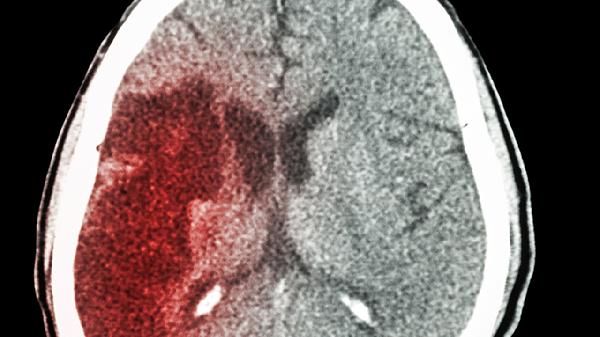

45岁正是事业黄金期,却突然栽倒在早餐桌上!你可能想不到,那些习以为常的早餐搭配,正在悄悄为血管“埋雷”。血管外科医生发现,近七成脑梗患者都有相似的早餐习惯。今天就来扒一扒那些伪装成“美味”的血管杀手。